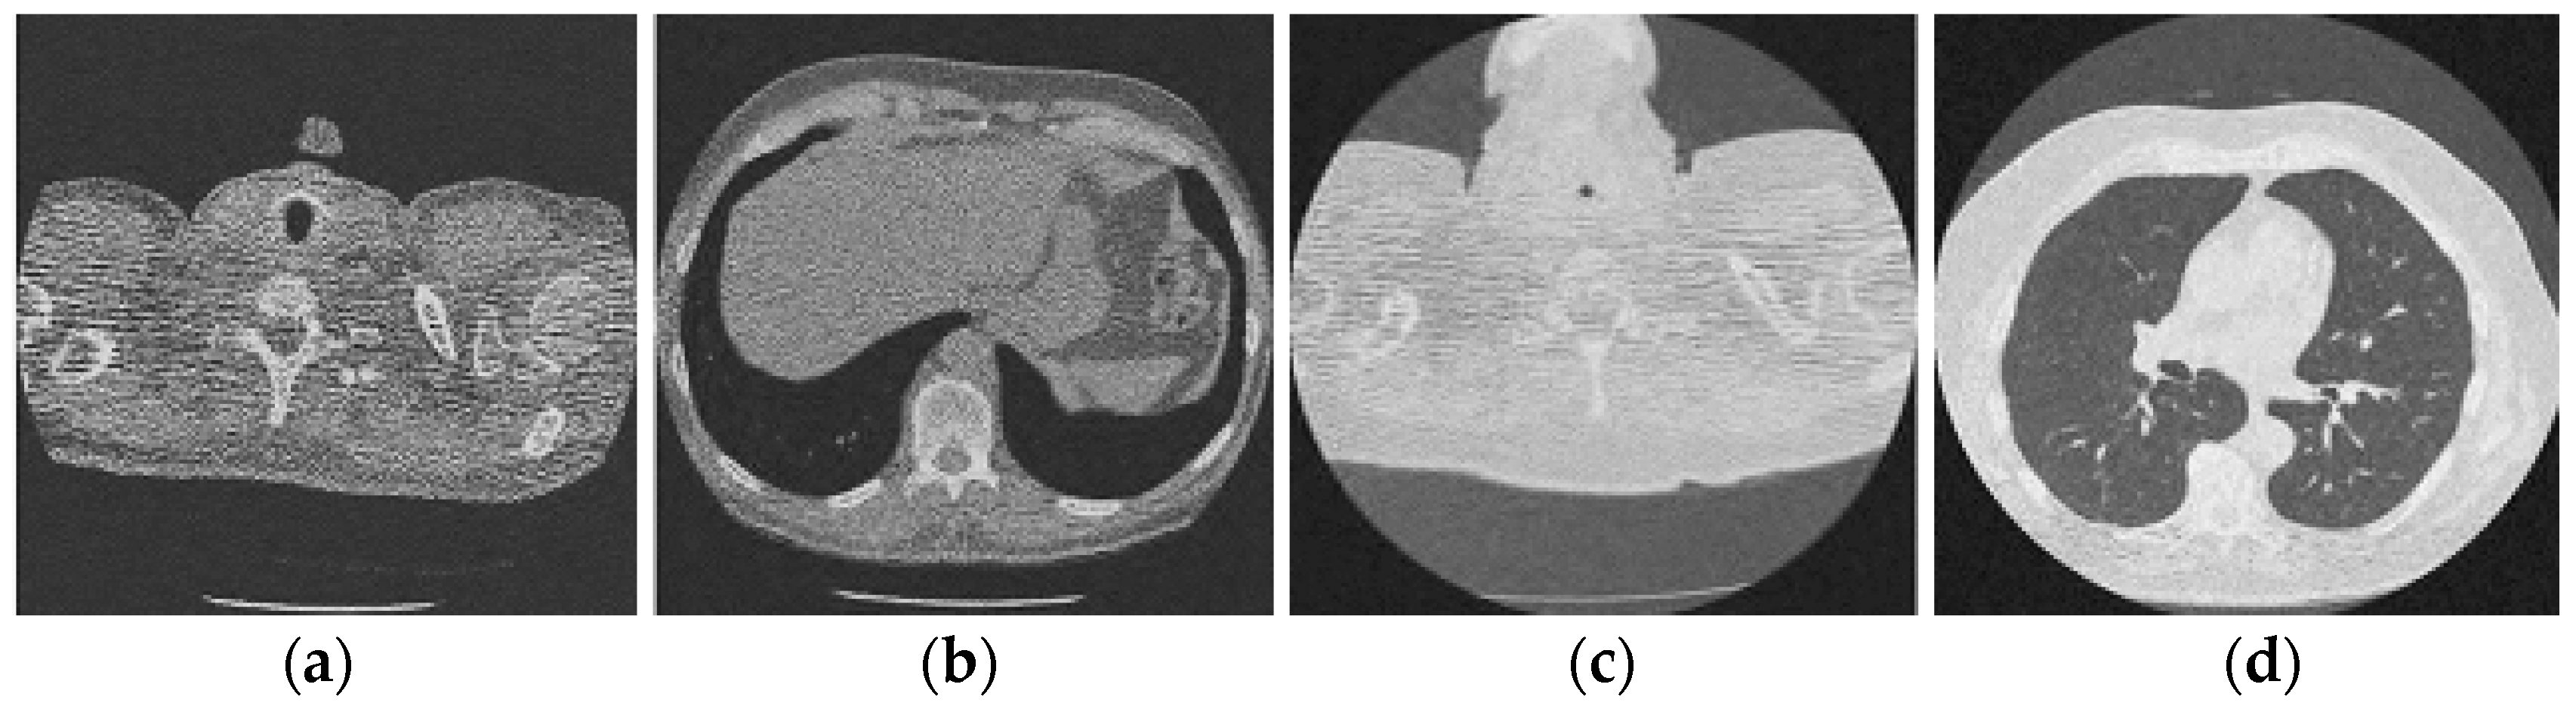

Figure 11.

Results of the proposed CT image denoising method; (a) Denoised CT1 image; (b) Denoised CT2 image; (c) Denoised CT3 image; (d) Denoised CT4 image.

For effective comparison to other systems available out there, this system has been pitted against seven of the most robust and widely used denoising techniques out there, i.e., Figure 4, Figure 5, Figure 6, Figure 7, Figure 8, Figure 9, Figure 10 and Figure 11. All the denoising frameworks performed reasonably well, with similar levels of denoising in their outputs, within a certain margin of error and variations. The result from these techniques for four CT images is displayed in Figure 4, Figure 5, Figure 6, Figure 7, Figure 8, Figure 9, Figure 10 and Figure 11. The CT image manipulation gave rise to redundant overcorrection, cumulating in distortion of the black borders and the introduction of fuzziness. Only two CT images from the rivaling systems have managed to preserve the blackness of the outer borders in the CT images. The result from [45] in Figure 9c is the least clear, with distortion visible to the unaided observer. A similar problem is observed in Figure 4a,c, where the system overcorrects, introducing more distortion instead of improving clarity. Figure 10d comes closest to the original, though the proposed framework is superior, as illustrated in the next section. From Figure 11a–d, it is very clear that the proposed algorithm gives better outcomes in comparison to existing methods in terms of clinical features, such as edges, textures, contrasts, and brightness.